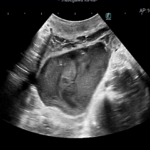

腹部超音波検査では前立腺実質エコーは均質であり、形状は通常左右対称である。前立腺炎の場合、実質は不均一であり、多巣性の低エコー領域が存在する。前立腺膿瘍および前立腺内嚢胞は局所的な単一または複数の無から低エコーの構造として現れる。